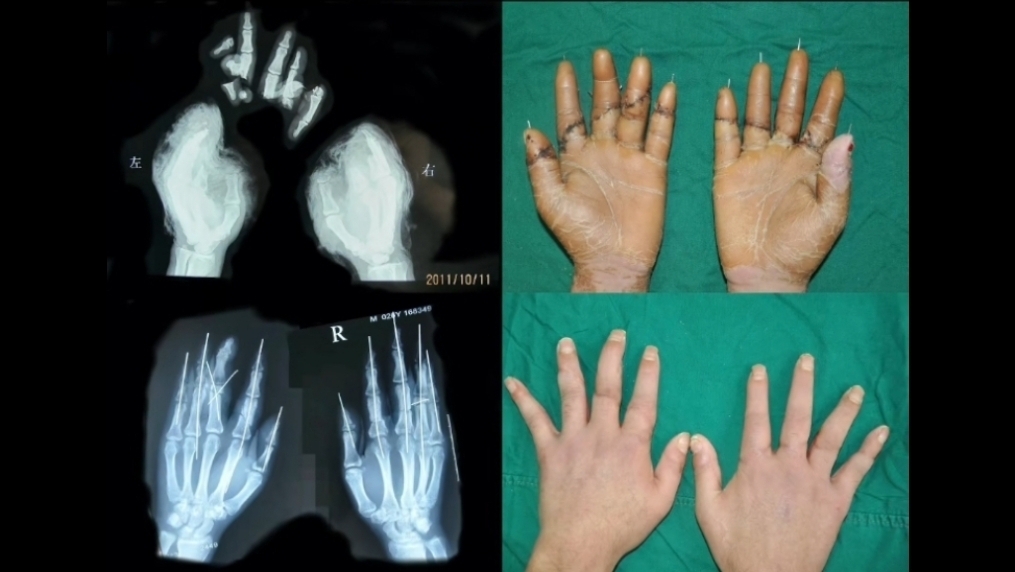

山東青島34歲的宮姓男子最近工作時因操作不慎,雙手十指被沖床液壓機完全截斷,十個手指從不同的水平面完全離斷,骨折和肌腱斷端外露傷口瞬間流血不止。他的慘叫聲迅速引來了同事,大家一邊照顧他,一邊收集被截斷的手指,盡快將他送院。院方了解情況後,緊急組建顯微外科手術團隊,10名醫生分三班齊上陣,經過17小時的努力,10個斷指全部被接活。目前,宮先生手指恢復狀態良好,已經出院。